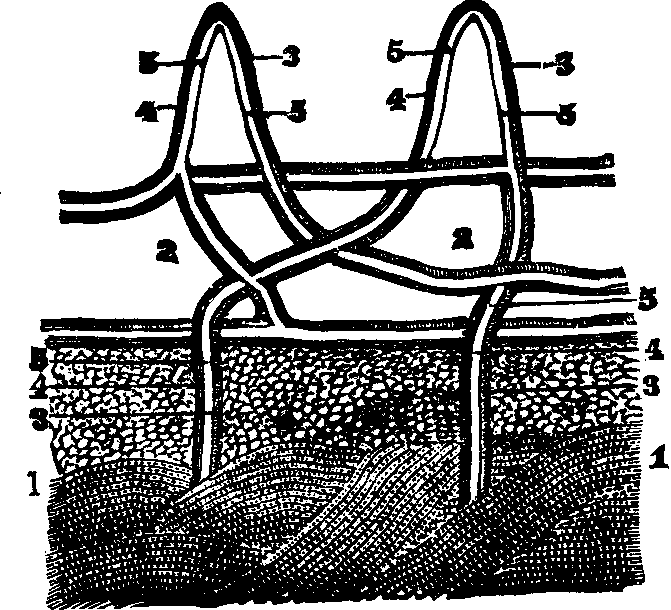

substance, and the arrangement of the pigmentary matter. C.

Transverse sections, showing the distinction between the cortical and

medullary substances, and the central collection of pigmentary matter,

sometimes found in the latter. Magnified 310 diameters.

Hairs are horny appendages of the skin, and, with the exception

of the hands, the soles of the feet, the backs of the fingers and toes,

between the last joint and the nail, and the upper eyelids, are distributed

more or less abundantly over every part of the surface of the body. Over

the greater part of the surface the hairs are very minute, and in some

places are not actually apparent above the level of the skin; but the hair

of the head, when permitted to reach its full growth, attains a length of

from twenty inches to a yard, and, in rare instances, even six feet. A hair